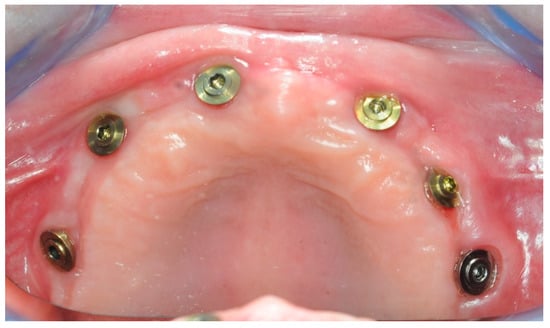

2.2. Surgery

2.3. Re-Entry Surgery

3.2. Surgical Guide Accuracy